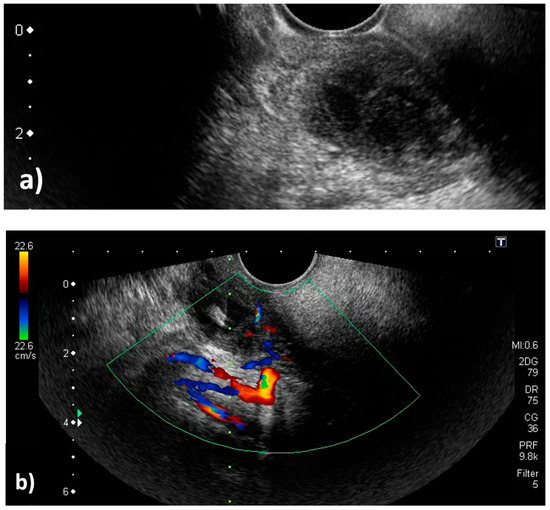

Figure 1.

Contrast-enhanced computed tomography. (a) Coronal view. (b) Axial view. The peritonsillar abscess is indicated by the yellow arrows.